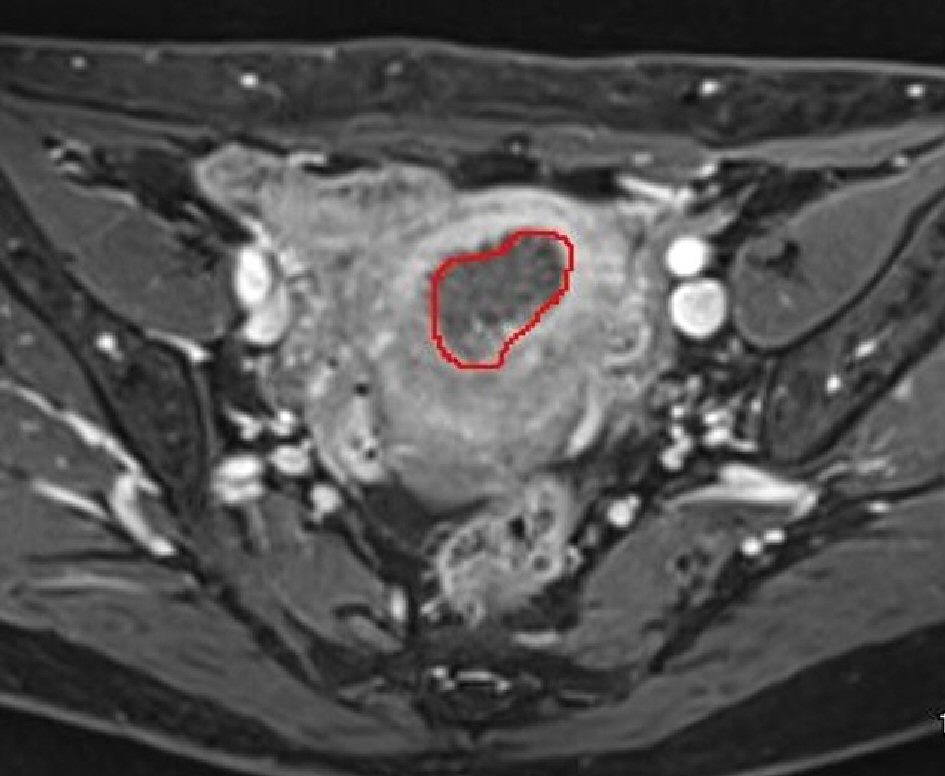

Image analysis and tumor volume setting

Tumor volume measurements were calculated using 3D-MRI with AqariusNET Server 4G software. Acquired MRI images were transferred to the software, which allowed for 3D views (Fig. 1) and volumetry. The tumor margins were determined from T2-weghted images or T1-weighted images enhanced by gadolinium, which showed tumor lesions more clearly. The first step for calculating the tumor volume is outlining the border of the tumors; we put region of interest (ROI) at the tumor manually. Using the volumetry function within the software, the outlined tumors are cored out, integrated, and the tumor volume is automatically calculated (Fig. 2). MRI finding of tumors were often varied, and there were some cases in which the tumors had necrosis or unclear boarder. In those cases we took the parts of tumors which were enhanced by gadolinium clearly. Under the direction of one expert radiologist with more than 20 years’ of experience, MRI findings were examined by one gynecologic oncologist with more than 10 years’ of experience. They were not involved in the clinical care. We performed ROI measurement twice with each case and took average of them. MR imaging was obtained on a 3Tesra system (Magnetom Verio, Siemens Healthcare, Erlangen, Germany) with 32-element body array coil. The protocol of our routine MR examination was as follows; T2WI (sagittal) (TSE: TR/TE = 4000/89, Matrix = 512/307, FOV = 200 × 200, ETL = 19, slice thickness = 3 mm), T1WI (axial) (SE: TR/TE = 450/12, Matrix = 320/192, FOV = 200 × 200, slice thickness = 3 mm), T2WI (axial) (SPACE: TR/TE = 2700/287, Matrix = 256/256, FOV = 250 × 250, slice thickness = 1.0 mm, flip angle mode = T2 var), HASTE (coronal)(TR/TE = 2000/88, Matrix = 320/240, FOV = 280 × 280, slice thickness = 5 mm). All cases underwent dynamic contrast-enhanced MRI with a dose of 10mL of meglumine gadopentetate (Magnevist®; Bayer, Germany), that was injected with an automated injector at a rate of 2 mL/s and followed by a 20mL saline flush. Dynamic MRI was performed at three continuous fat saturated T1 weighted images (axial) (VIBE: TR/TE = 3.74/1.38, FA = 11, Matrix = 256/256, FOV = 250 × 200, slice thickness = 1.0 mm) in 60, 120, 180 s after injection. These diagnostic imaging modalities are acceptable for excluding the possibility of malignancy before surgery and choosing appropriate treatment option.

![]() Click for large image | Figure 1. Using 3D-MRI reconstructions complete visualization of the pelvis is possible. |

![]() Click for large image | Figure 2. The border of tumors is outlined and the outlined tumors are cored out, integrated, and the tumor volume is automatically calculated using the volumetry function. |